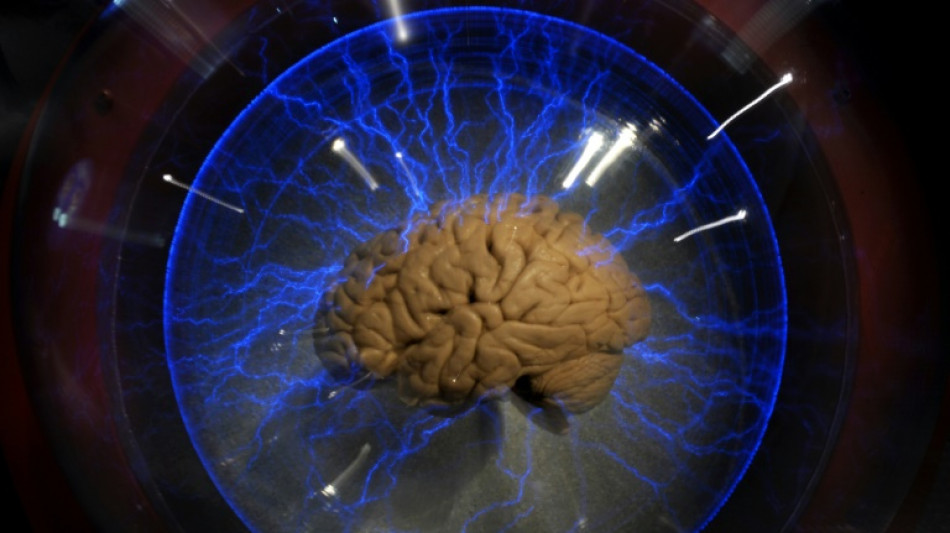

Una neuroprótesis permite expresarse a un hombre paralizado

Un hombre paralizado, incapaz de hablar o escribir a máquina, ha conseguido expresar más de mil palabras gracias a una neuroprótesis que traduce sus ondas cerebrales en frases, anunciaron el martes investigadores estadounidenses.

Los investigadores le implantaron un electrodo de alta intensidad en el cerebro en 2019, por encima del córtex motor responsable del habla.

Ahora detectan los impulsos eléctricos que se generan allí cuando el paciente intenta hablar.